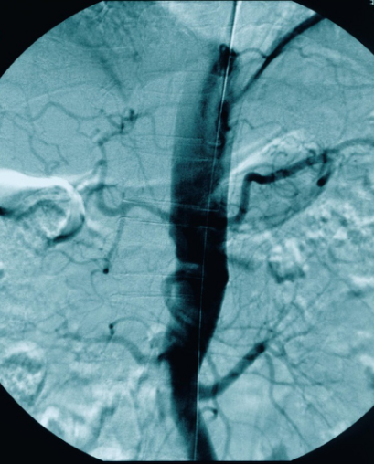

男性、58岁,间跛100米、慢性下肢缺血,病史3年

造影提示患者为长段闭塞,如果一期行腔内治疗,则累及肾动脉;所以行预置导管溶栓,后行支架术,血流重建效果显著。